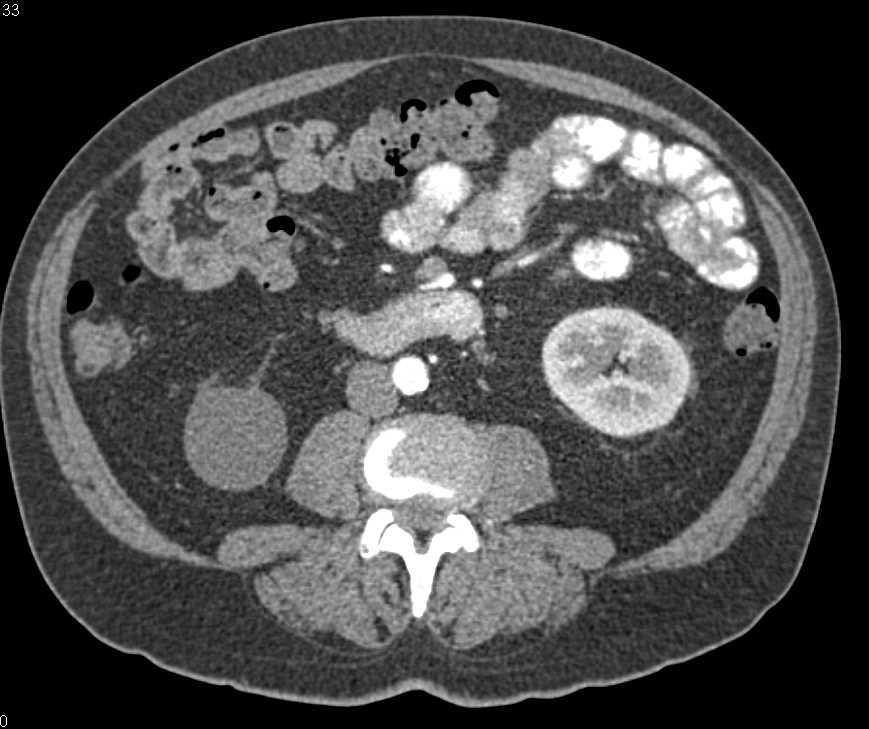

Acute Pyelonephritis Right Kidney